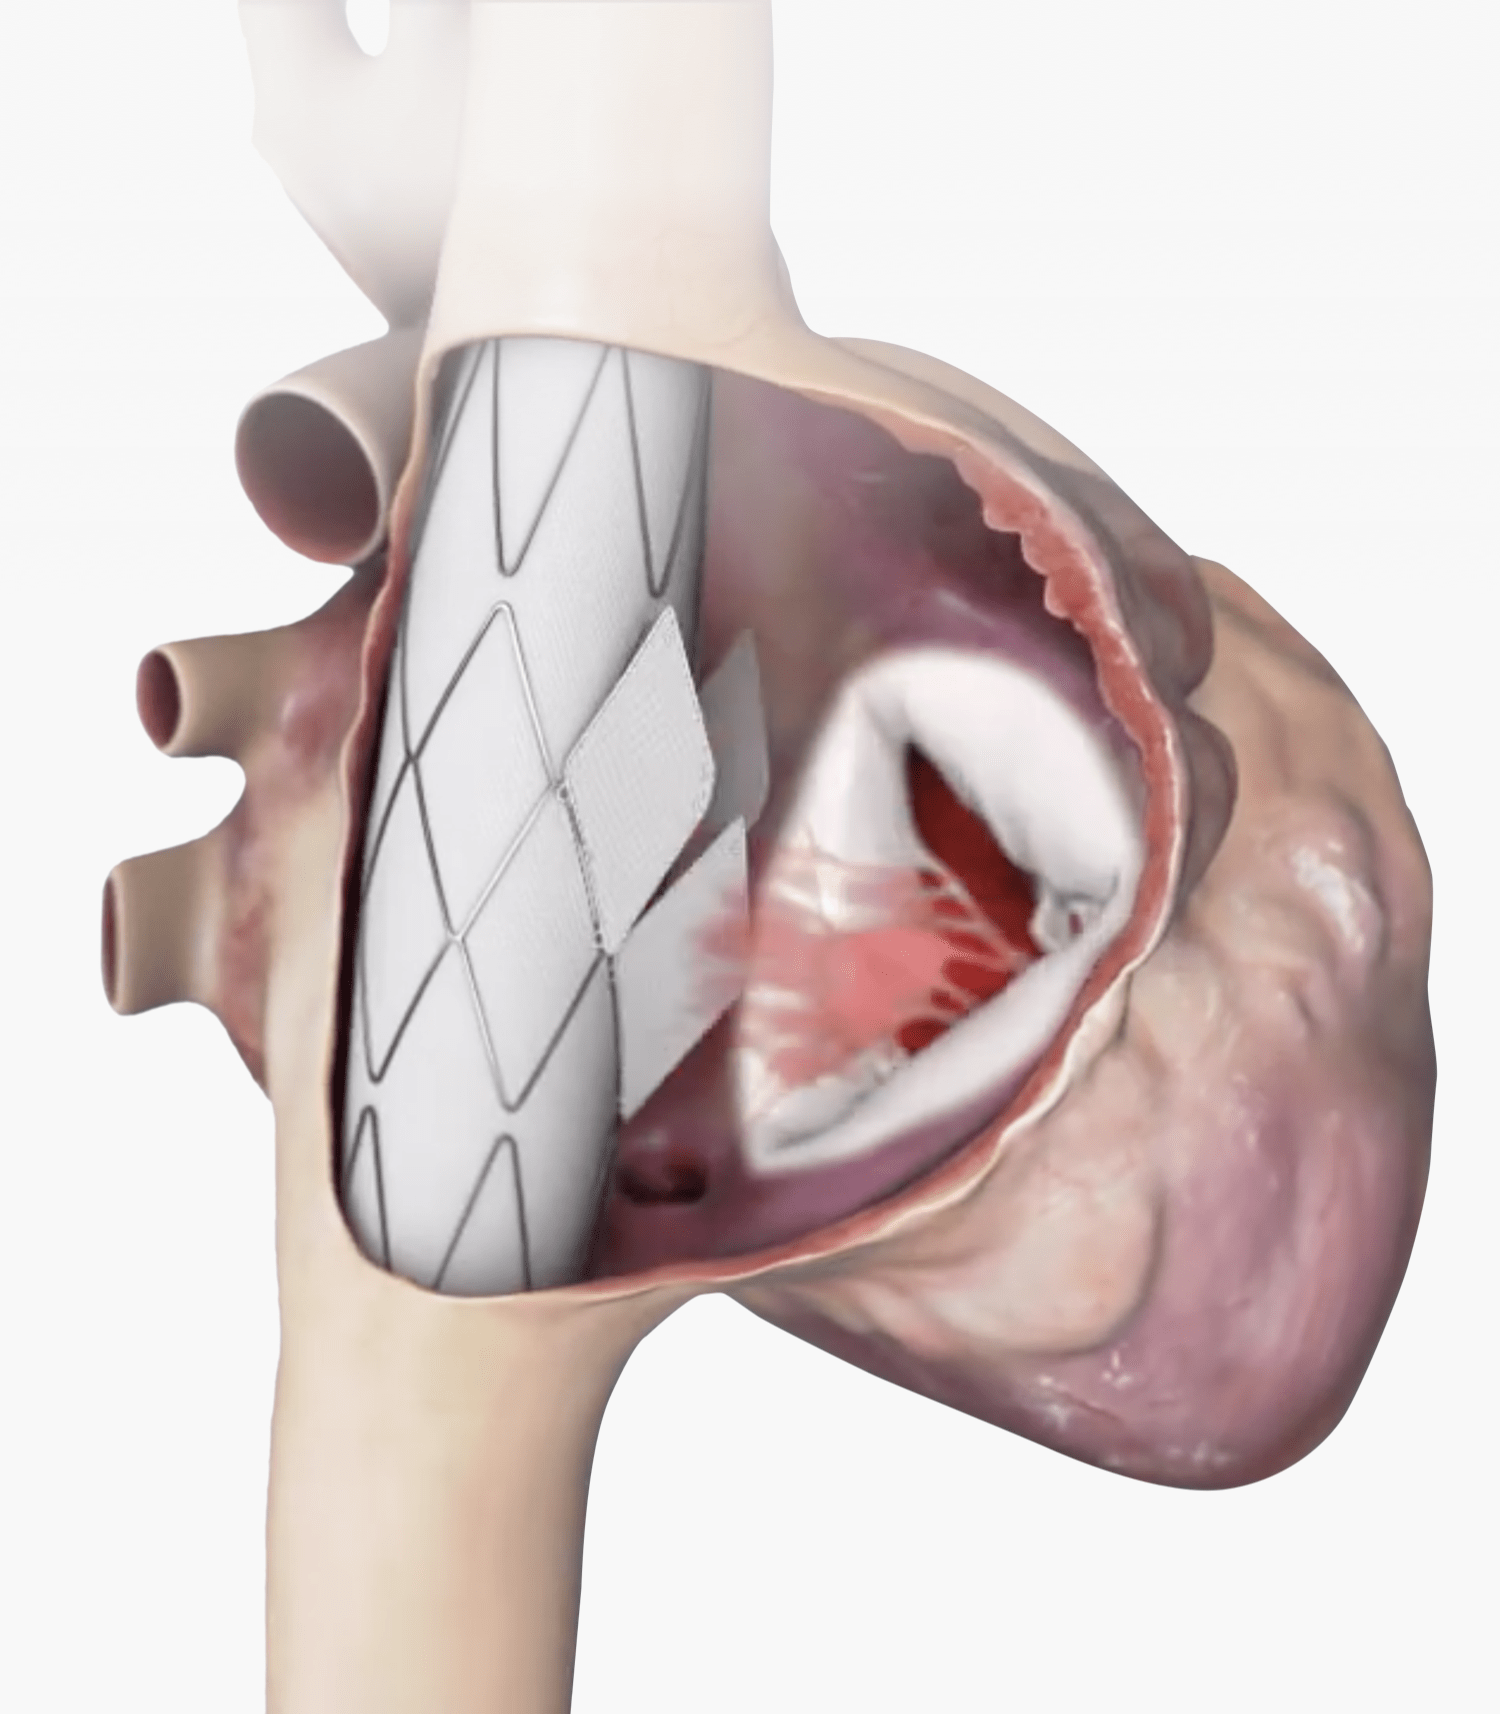

Trillium™ is meticulously crafted for the unique demands of the tricuspid valve environment.

This stent graft, featuring a valved wall, is designed to span the right atrium with secure fixation

in the Superior Vena Cava (SVC) and Inferior Vena Cava (IVC), leaving the native valve untouched.

Multiple, Normally Open Valves

Provide extremely low filling

(diastolic) pressures, with an

increased closing volume for the

benefit of patients with RV failure.

Large Flange Sealing Skirt

Creates a secure seal that fits a wide

range of anatomies, while allowing

the necessary hepatic vein inflow.

Mechanically Durable

Designed for long-term fatigue

resistance. Durable for decades of

Radio-Opaque Markers

Ensure precise positioning under a

strictly fluoroscopic procedure.

Atraumatic Stent Ends

Provides reliable anchoring,

reducing the risk of complications

during and after the procedure.

Low Profile Delivery System

24 Fr delivery system for

venous transfemoral approach.